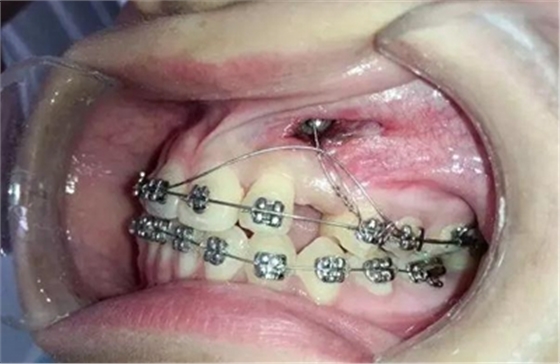

幾天過后病人向我反應(yīng)側(cè)切牙壓痛松動

我考慮一下應(yīng)該是尖牙牙冠壓迫壓迫側(cè)切牙的根尖部導(dǎo)致的疼痛和松動

考慮到如果能像種植支抗,水平方向或者向唇側(cè)牽引移動,可以有效避免垂直方向牽引力壓迫側(cè)切牙根尖部,所以我和病人溝通了一下,建議采用種植支抗,但是病人不想增加費用。

那好吧還是采用輔弓增加支抗,經(jīng)濟適用,也便與操作,0.8不銹鋼絲彎制,進行熱處理,增加其彈力。